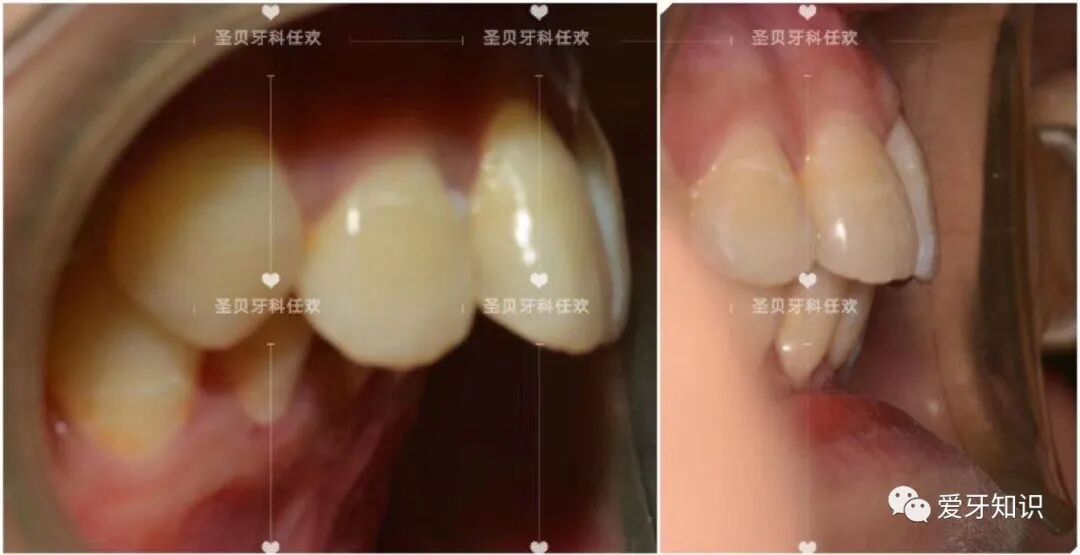

像这样的龅牙+嘴凸矫正变化就很大。于是拔掉了4颗正畸牙然后内收牵引,达到嘴型变化的过程!https://mmbiz.qpic.cn/mmbiz_png/fwaTu5a4jNI7P9JsNol5Bntcf4QDLzTxjUPJxibamWl8FlvEjBXATic1e69qaO5R2qEFh1OB2ddeaiam3YD4biaZAQ/640?wx_fmt=png

下面来看看我们两个人的矫正变化吧!

我的变化。

他的变化。